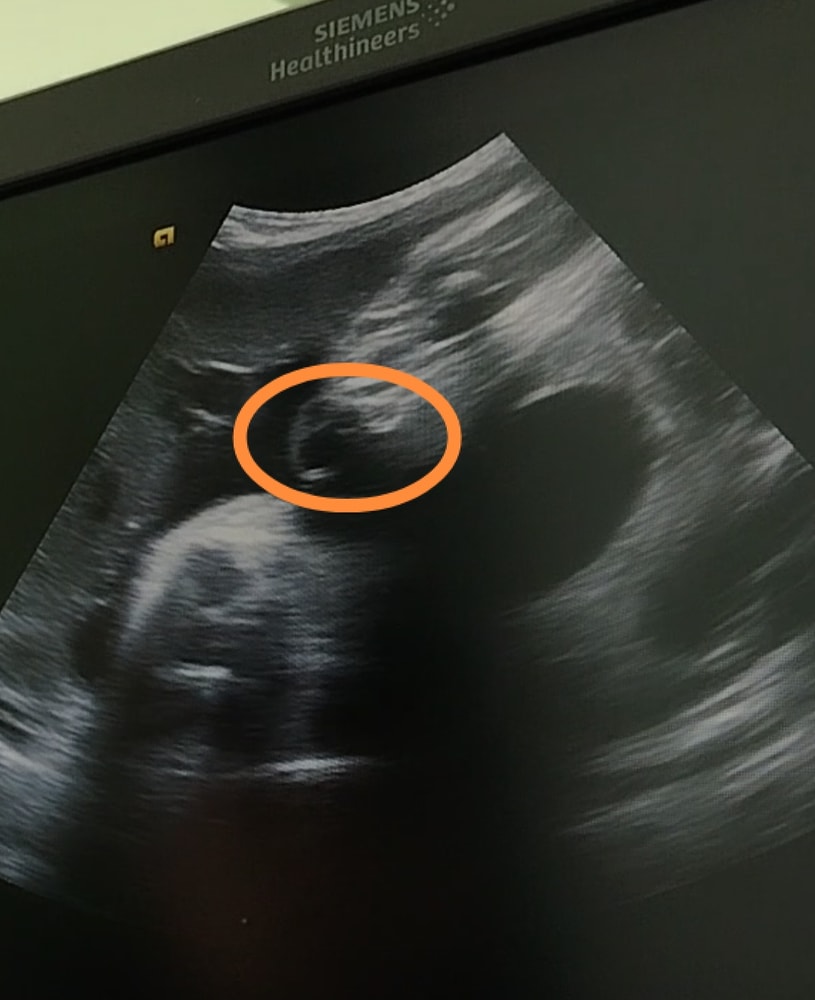

Ирина Лапина, я, честно говоря, вообще плохо понимаю, что на снимке. Вот этот предполагаем пенис вполне может быть пуповиной.

Ирина Лапина, почему обрезанная? Просто на узи такой срез виден)

Это ведь не 3Д)